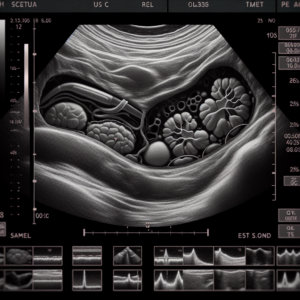

מה חשוב לדעת על הריון בגיל מבוגר וסקירה מוקדמת

בעשורים האחרונים אנו עדים למגמה הולכת וגוברת של נשים הבוחרות להרות בגיל מאוחר יותר. שיקולים קרייריסטיים, כלכליים, רגשיים ואישיים מובילים נשים רבות לדחות את ההריון

מכון אולטרסאונד פרטי

הבלוג בוחן את התפקיד המרכזי של מכוני אולטרסאונד פרטיים בתחום הבריאות המודרני. הוא מתעמק בשירותים השונים שהם מציעים, הטכנולוגיה שהם משתמשים בהם, וכיצד הם תורמים